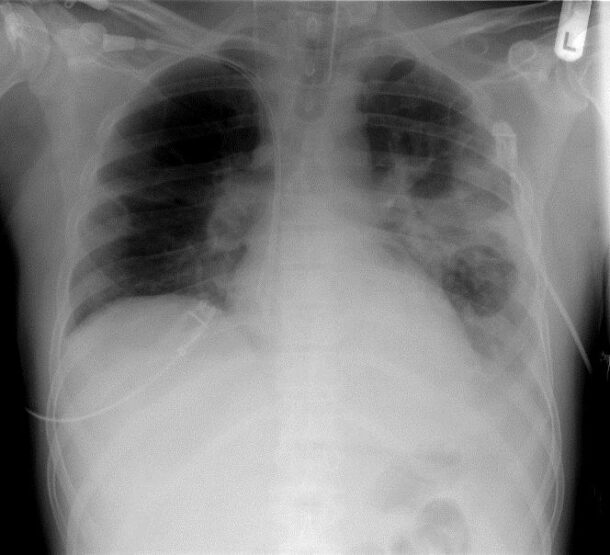

Inzwischen konnte ich noch weitere Erfahrungen mit Natrium sulfuricum C200 sammeln. Es half nicht nur bei Lungenentzündungen, die kurz vor der Krankenhauseinweisung waren (völlige Heilung eines schwerkranken 5jährigen Mädchens als auch bei einem 82jährigen Patienten) als auch bei beginnenden Mittelohrentzündungen und Hautausschlägen begleitet von der Influenza. Bei diversen Fällen konnte der Ausbruch der Influenza (Familienmitglieder hatten eine diagnostizierte Influenza) bei sofortiger Gabe von Natrium sulfuricum C200 sogar gestoppt werden, als sie plötzlich Halsschmerzen und Schwäche bekamen.